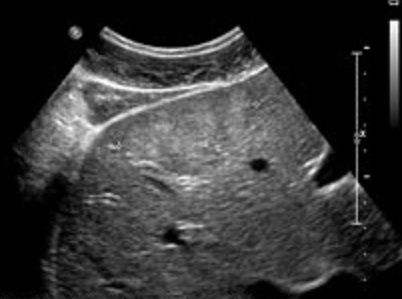

Aspect hypoechogen des

metastases cancereuse du foie |

Aspect de reverse

hyperchogene des metastases du foie |